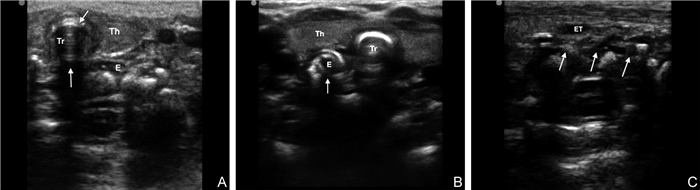

目的  探讨超声成像技术评估危重早产儿气管内插管定位的临床应用效果。  方法  选择2019年1月—2021年1月于南京医科大学第一附属医院新生儿监护病房住院并接受气管内插管术的103例早产儿为研究对象,以定位气管内插管方式的不同,分为超声定位组(50例)和以听诊肺部及胃泡判断气管导管在位的对照组(53例),导管固定后均采用胸部X线评估导管的位置。观察并分析超声组声像图特征,比较组间定位气管导管适宜率、误入食管率、误入主支气管(置管过深)率、脱管(置管过浅)率,评价2种方式定位导管的准确性。  结果  超声组定位导管适宜率(86.0% vs. 54.7%, P=0.001)高于对照组,误入主支气管率(6.0% vs. 20.8%, P=0.029)、脱管率(4.0% vs. 17.0%, P=0.033)低于对照组;以X线定位气管导管位置适宜为金标准,2组定位方式为筛查标准,发现超声组定位灵敏度(91.1% vs. 88.9%)、特异度(80.0% vs. 11.8%)、约登指数(71.1% vs. 6.5%)及Kappa一致性系数(0.561 vs. 0.008)均明显高于对照组。  结论  超声成像技术评估气管导管定位实时、有效,可准确判断导管位置及深度,减少放射性暴露累积,值得在危重早产儿中推广应用。